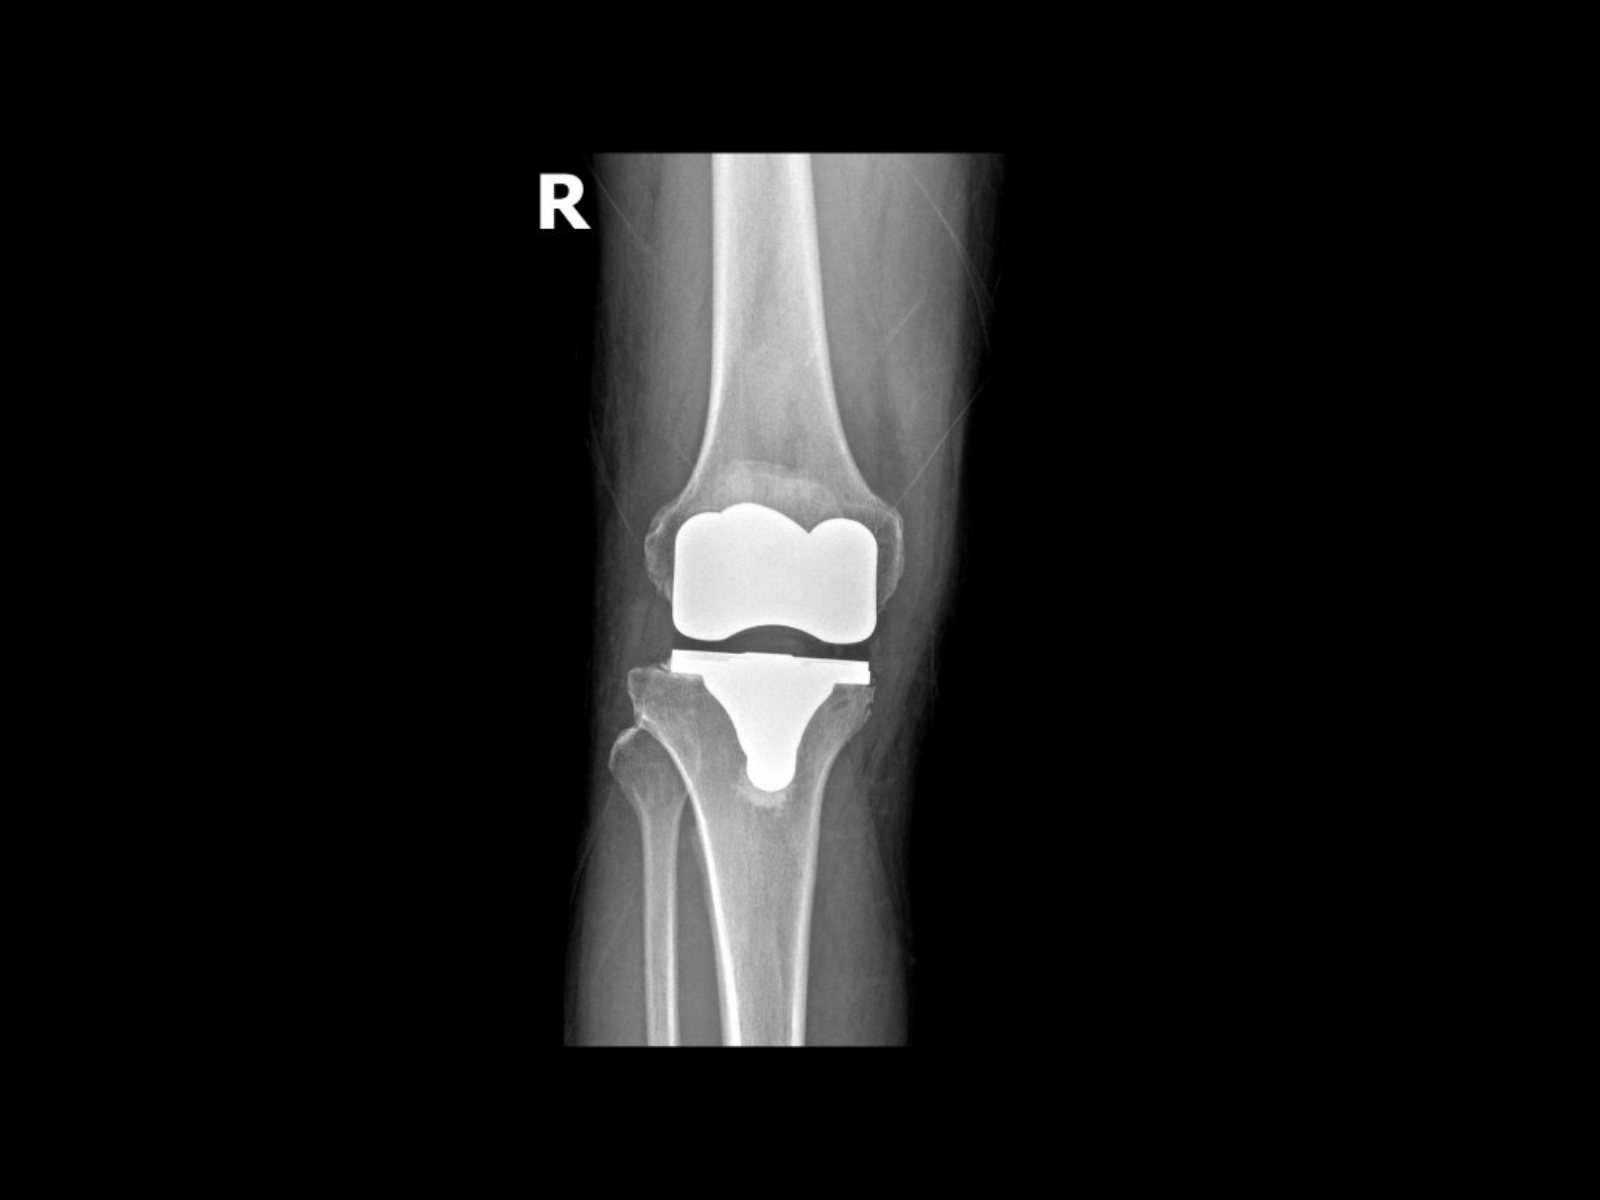

- Kết quả chụp X-quang cho thấy khớp gối bị hư hại nhiều. Tuy nhiên, một số trường hợp người bệnh không đau nhưng bị biến dạng chân nhiều, ảnh hưởng đến chức năng và trục chi cũng có thể được chỉ định thay khớp gối.

- Thay khớp gối toàn phần: Là giải pháp điều trị cuối cùng, hiệu quả cao với những người bệnh thoái hóa khớp gối nặng ở giai đoạn III và IV, điều chỉnh hoàn hảo các biến dạng khớp. Sau phẫu thuật, người bệnh sẽ được cải thiện triệu chứng đau, tránh nguy cơ tàn tật vĩnh viễn.

- Thay khớp gối bán phần: Là sự lựa chọn thích hợp cho khớp gối không bị hư hoàn toàn. Chỉ cần một ngăn của khớp gối bị hư là đã phải thay, có thể ngăn ngoài hay ngăn trong, giữ lại những ngăn còn tốt. Phẫu thuật này thường nhẹ hơn so với thay khớp gối toàn phần, thời gian phục hồi sau thay khớp gối cũng ngắn hơn.